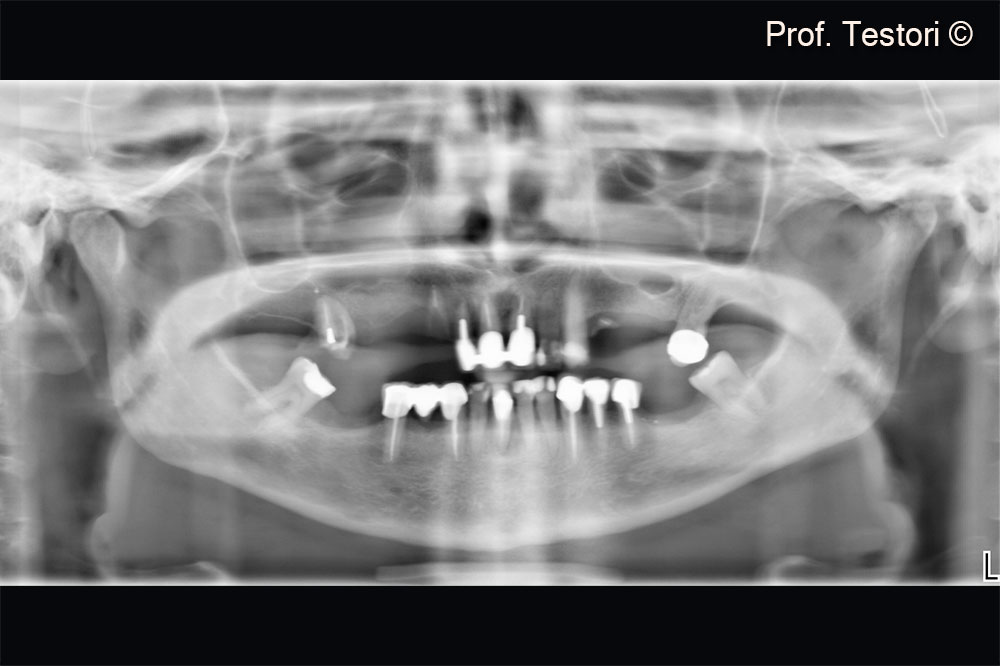

Pre-operative radiograph